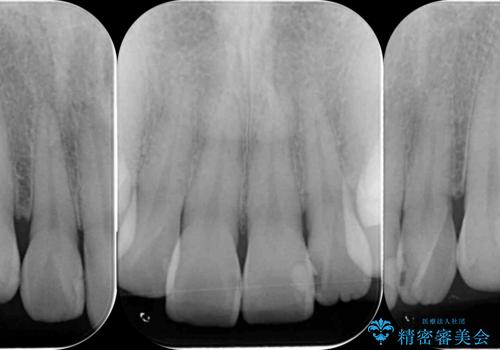

視診、X線写真より前歯に発生した大きな虫歯が認められました。